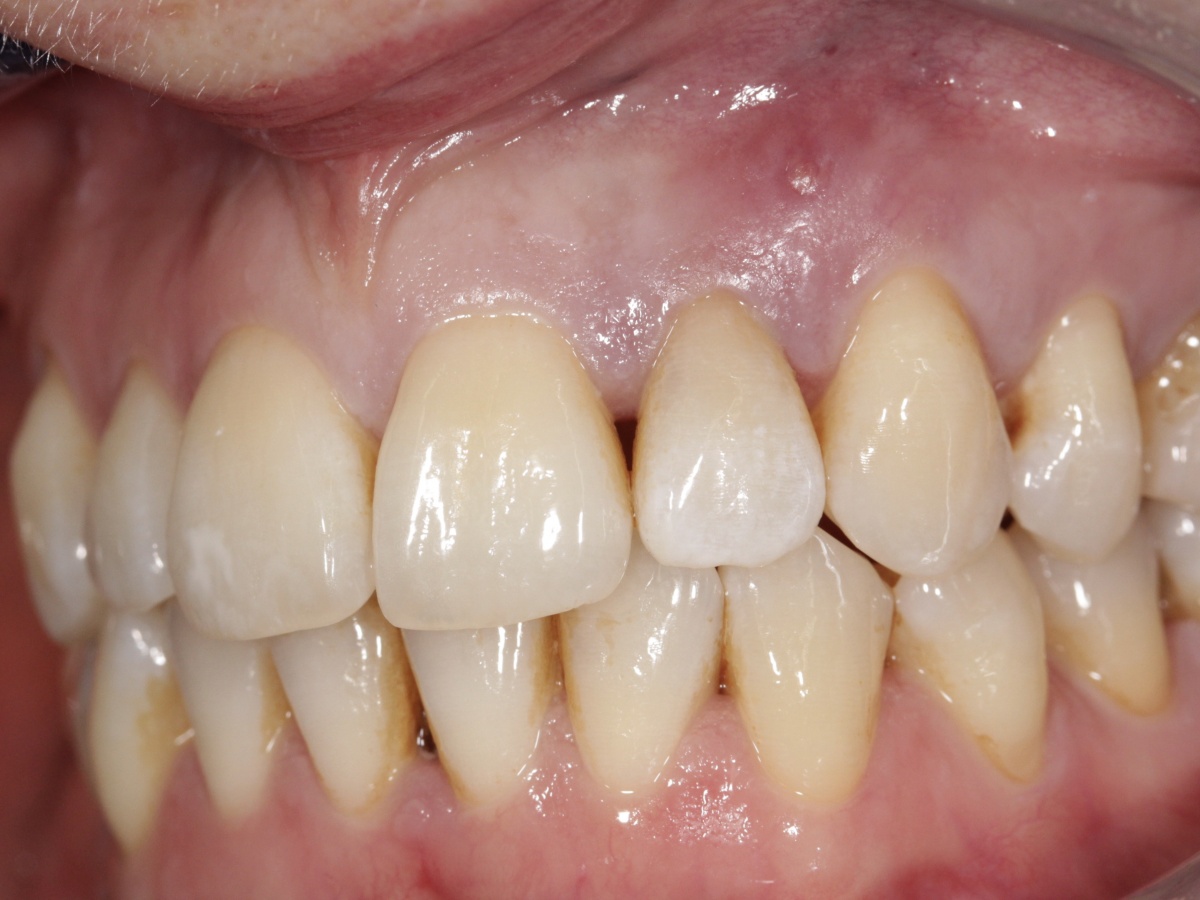

Im Januar 2019 stellte sich ein 52-jähriger Soldat mit einem auf Gingivaniveau abgebrochenen Zahn 21 im Rahmen einer Notfallbehandlung bei uns vor. Zur Wiederherstellung der Ästhetik, Phonetik und Beißfunktion wurde die Krone in direktem Verfahren wieder aufgebaut. Das anschließend angefertigte Röntgenbild zeigte eine zu kurze und inhomogene Wurzelfüllung mit Hinweisen auf eine vorliegende Via falsa.

Gleichzeitig berichtete der Patient über Beschwerden am Zahn, welche wiederholt auftraten und sich durch Druck auf das Vestibulum reproduzieren ließen. Eine Schwellung, Fistelung oder erhöhte Sondierungswerte lagen zu diesem Zeitpunkt nicht vor. Da zur Aufnahme einer laborgefertigten Restauration eine vorherige Stiftinsertion geplant war, vereinbarten wir zunächst die Revision der vorhandenen insuffizienten Wurzelfüllung. Trotz Dentalmikroskop und vorgebogenen Ultraschallfeilen ließ sich der ursprüngliche Kanalverlauf während der Revisionsbehandlung nicht mehr darstellen (Abb. 3 zeigt den Verlauf der Via falsa).

Nach eingehender Aufklärung des Patienten, entschieden wir uns für die Obturation des Wurzelkanals und der Via falsa sowie zur simultanen chirurgischen Entfernung der Wurzelspitze. Ziel war es auch, den nicht mechanisch und chemisch aufbereiteten Wurzelkanalanteil zuverlässig zu entfernen.